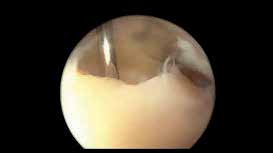

Das Sprunggelenk ist mittels Arthroskopie gut zu erreichen. Durch die oft posttraumatisch bedingten lokalen Knorpelschäden oder Osteonekrosen kann primär eine alleinige arthroskopische Therapie erfolgreich sein. Das reine Gelenkdebridement wird jedoch kontrovers diskutiert und zeigt analog zu den wissenschaftlichen Untersuchungen am Kniegelenk zur Gelenklavage bei Gonarthrose keine langfristige Schmerzlinderung 34. Dagegen kann beim Vorliegen ätiologisch bedingter degenerativer Gelenkveränderungen wie osteophytären Anbauten, freien Gelenkkörpern, vernarbter und hypertroph-entzündlicher Synovia oder fokalen osteochondralen Defekten (Abb. 5) durch das gezielte operative Gelenkdebridement eine signifikante und langfristige Schmerzreduktion erreicht werden 35.